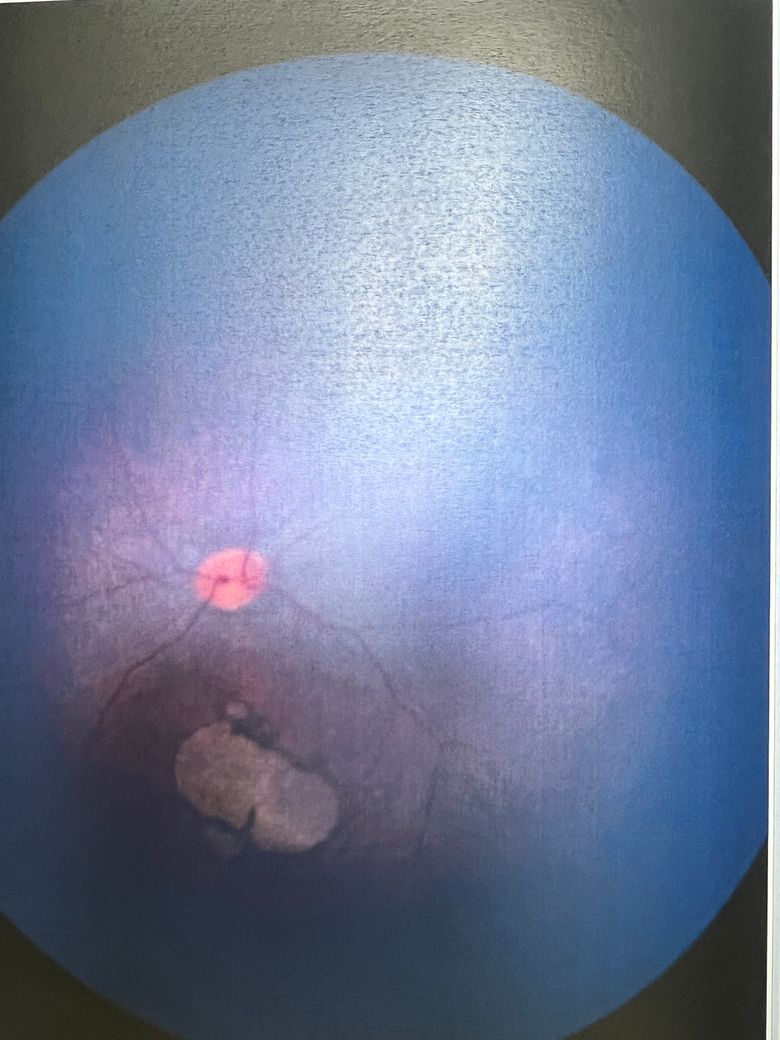

기다리는게 너무 답답해서 다른 대학병원 추가 검진 예정인데 오른쪽 왼쪽 안저검사 사진 첨부합니다.

• 1번 째 사진

우선 황반부 주변에 하얗게 보이는 부분 관련 황반부 시신경 부족이나 망막 변성을 의심할 수 있는 소견을 받으셨다 하셨고, 유전성 망막 질환(황반이영양증, 망막색소변성증 등)이 의심되고 있다구요.

이 경우 황반부 이상은 중앙 시야에 영향을 줄 수 있어 주의가 필요하지만, 정확한 심각성은 유전자 검사 결과와 추가 검진(OCT, ERG 등)을 통해 확인해야 합니다